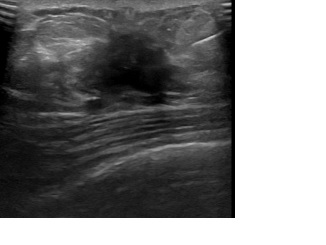

상기환자는 외부건진이상소견 정밀검사위해 내원하신 60대 중반

여성분으로 의심스러운 우측혹 조직검사 시행해 유방암 진단되었습니다.